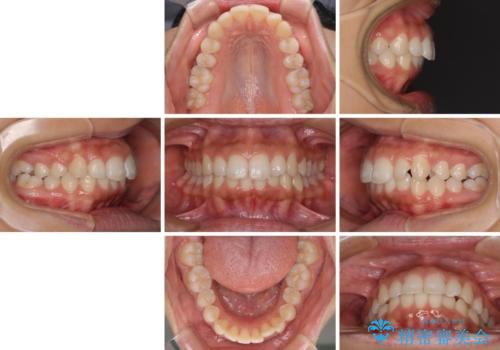

- 出っ歯で唇が閉じにくいとのことで来院された患者様です。

顎先に力を入れないと唇が閉じきれない口元であったので、上下左右の第一小臼歯4本を抜歯して、ワイヤー装置にて矯正治療を行うこととしました。

2年から2年半の治療期間を想定しており、予定通りの期間で無事に終了することができました。

唇や顎先に力を入れないなくてもスムーズに唇を閉じることができるようになりました。